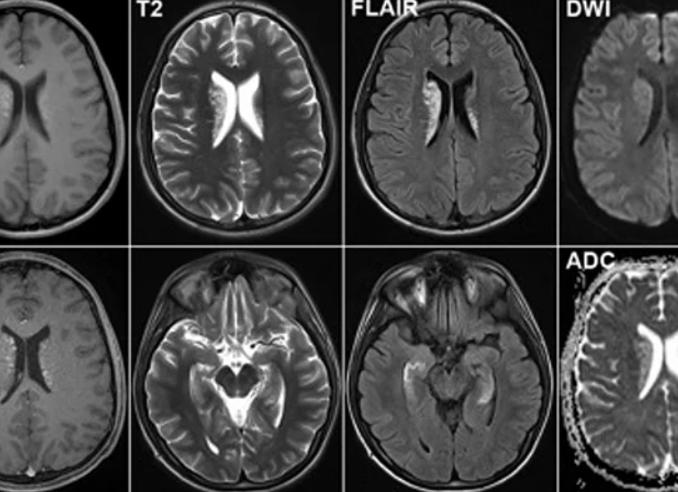

Разница изображений до и после выполнения контрастирования при МРТ головного мозга.

Магнитно-резонансная томография — это метод диагностики, использующий магнитное поле, радиочастотные импульсы и технологии компьютерной обработки для получения подробных изображений тела. МРТ с контрастом выполняют, если необходимо получить более четкие снимки.

На этих томограммах врач лучше видит анатомическую структуру органов, лимфатические пути и особенности кровотока.